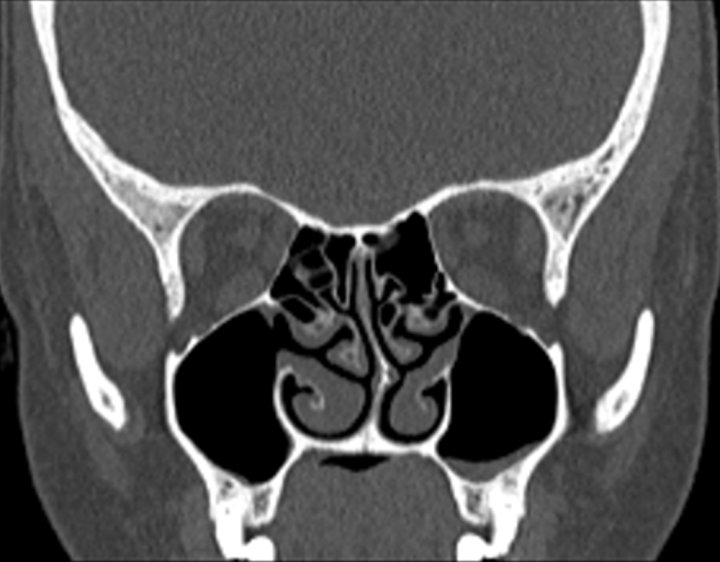

Click any image for labels.